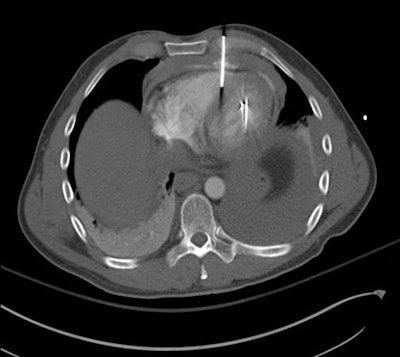

Shot to the chest

Though not as common as blunt trauma, penetrating trauma to the chest -- most frequently caused by a gunshot wound -- is associated with a considerably higher mortality rate, Nicolaou noted. Possible methods for the diagnostic evaluation of patients who do not require immediate surgery include chest x-ray, CT, echocardiography, and focused abdominal sonography in trauma (FAST).

X-ray was once the most widely used test for first-line diagnostic imaging, but advancements in CT technology have contributed to its rising use as the preferred modality in cases of penetrating trauma, he said. In particular, biphasic CT angiography (CTA) is well-suited to the task of highlighting potentially fatal injuries to the many arteries and veins in the chest.

There are three distinguishing signs on patients with penetrating trauma that prompt urgent evaluation with CTA as opposed to other imaging modalities:

- A central penetrating injury to the chest

- The presence of an artifact on the opposite side of its entry point into the chest

- Entry sites with corresponding exit sites

- Heart: Penetrating trauma located within the "cardiac box," which covers the area between the nipples from the clavicle to the bottom of the rib cage, usually indicates significant cardiac injury. Clinicians should perform urgent, dedicated cardiac CT for such cases to confirm the need for surgical intervention, Nicolaou noted.